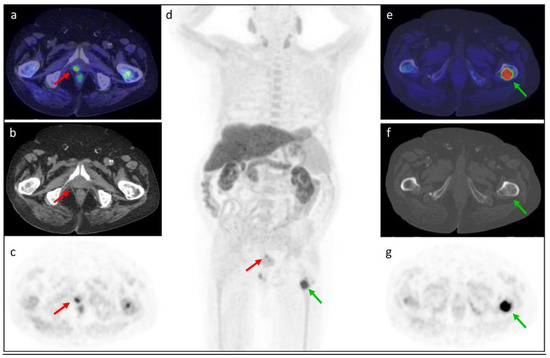

3.5. Clinical Cases